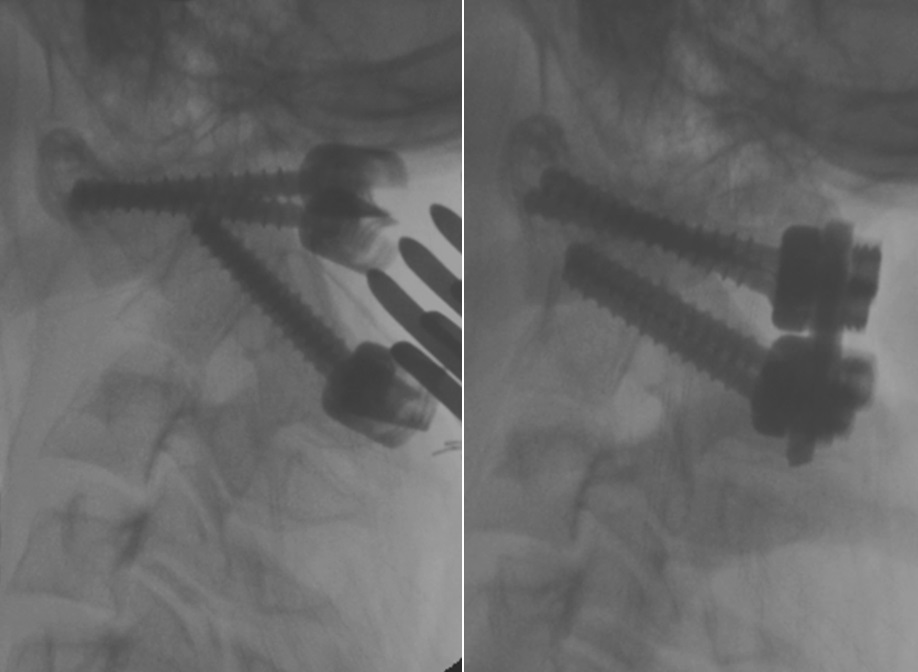

Chính vì những ưu điểm trên, ngày nay trên thế giới, kỹ thuật của Harms đã được coi là sự lựa chọn tối ưu cho các trường hợp mất vững khớp đội - trục. Từ năm 2011, Khoa Ngoại thần kinh - Hubet com cá cược thể thao Trung ương Hubet7788 trò chơi trực tuyến 108 đã triển khai kỹ thuật này. Hiện nay, kỹ thuật đã được áp dụng thường quy cho các mất vững khớp đội - trục do các nguyên nhân khác nhau: Chấn thương, viêm khớp dạng thấp, lao... mang lại kết quả tốt.

Hình ảnh minh họa